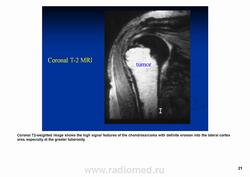

Рентгенологически выявляют в очаге деструкции участки обызвествления в виде крапчатости; кортикальный слой с признаками эрозии со стороны эндоста и истончения; размеры опухоли более 4 см; периостальная реакция слабо выражена или отсутствует; может наблюдаться деструкция кортикальной кости и наличие мягкотканного компонента; в длинных костях локализуется чаще в метафизах и диафизах; интенсивное внутрикостномозговое распространение.